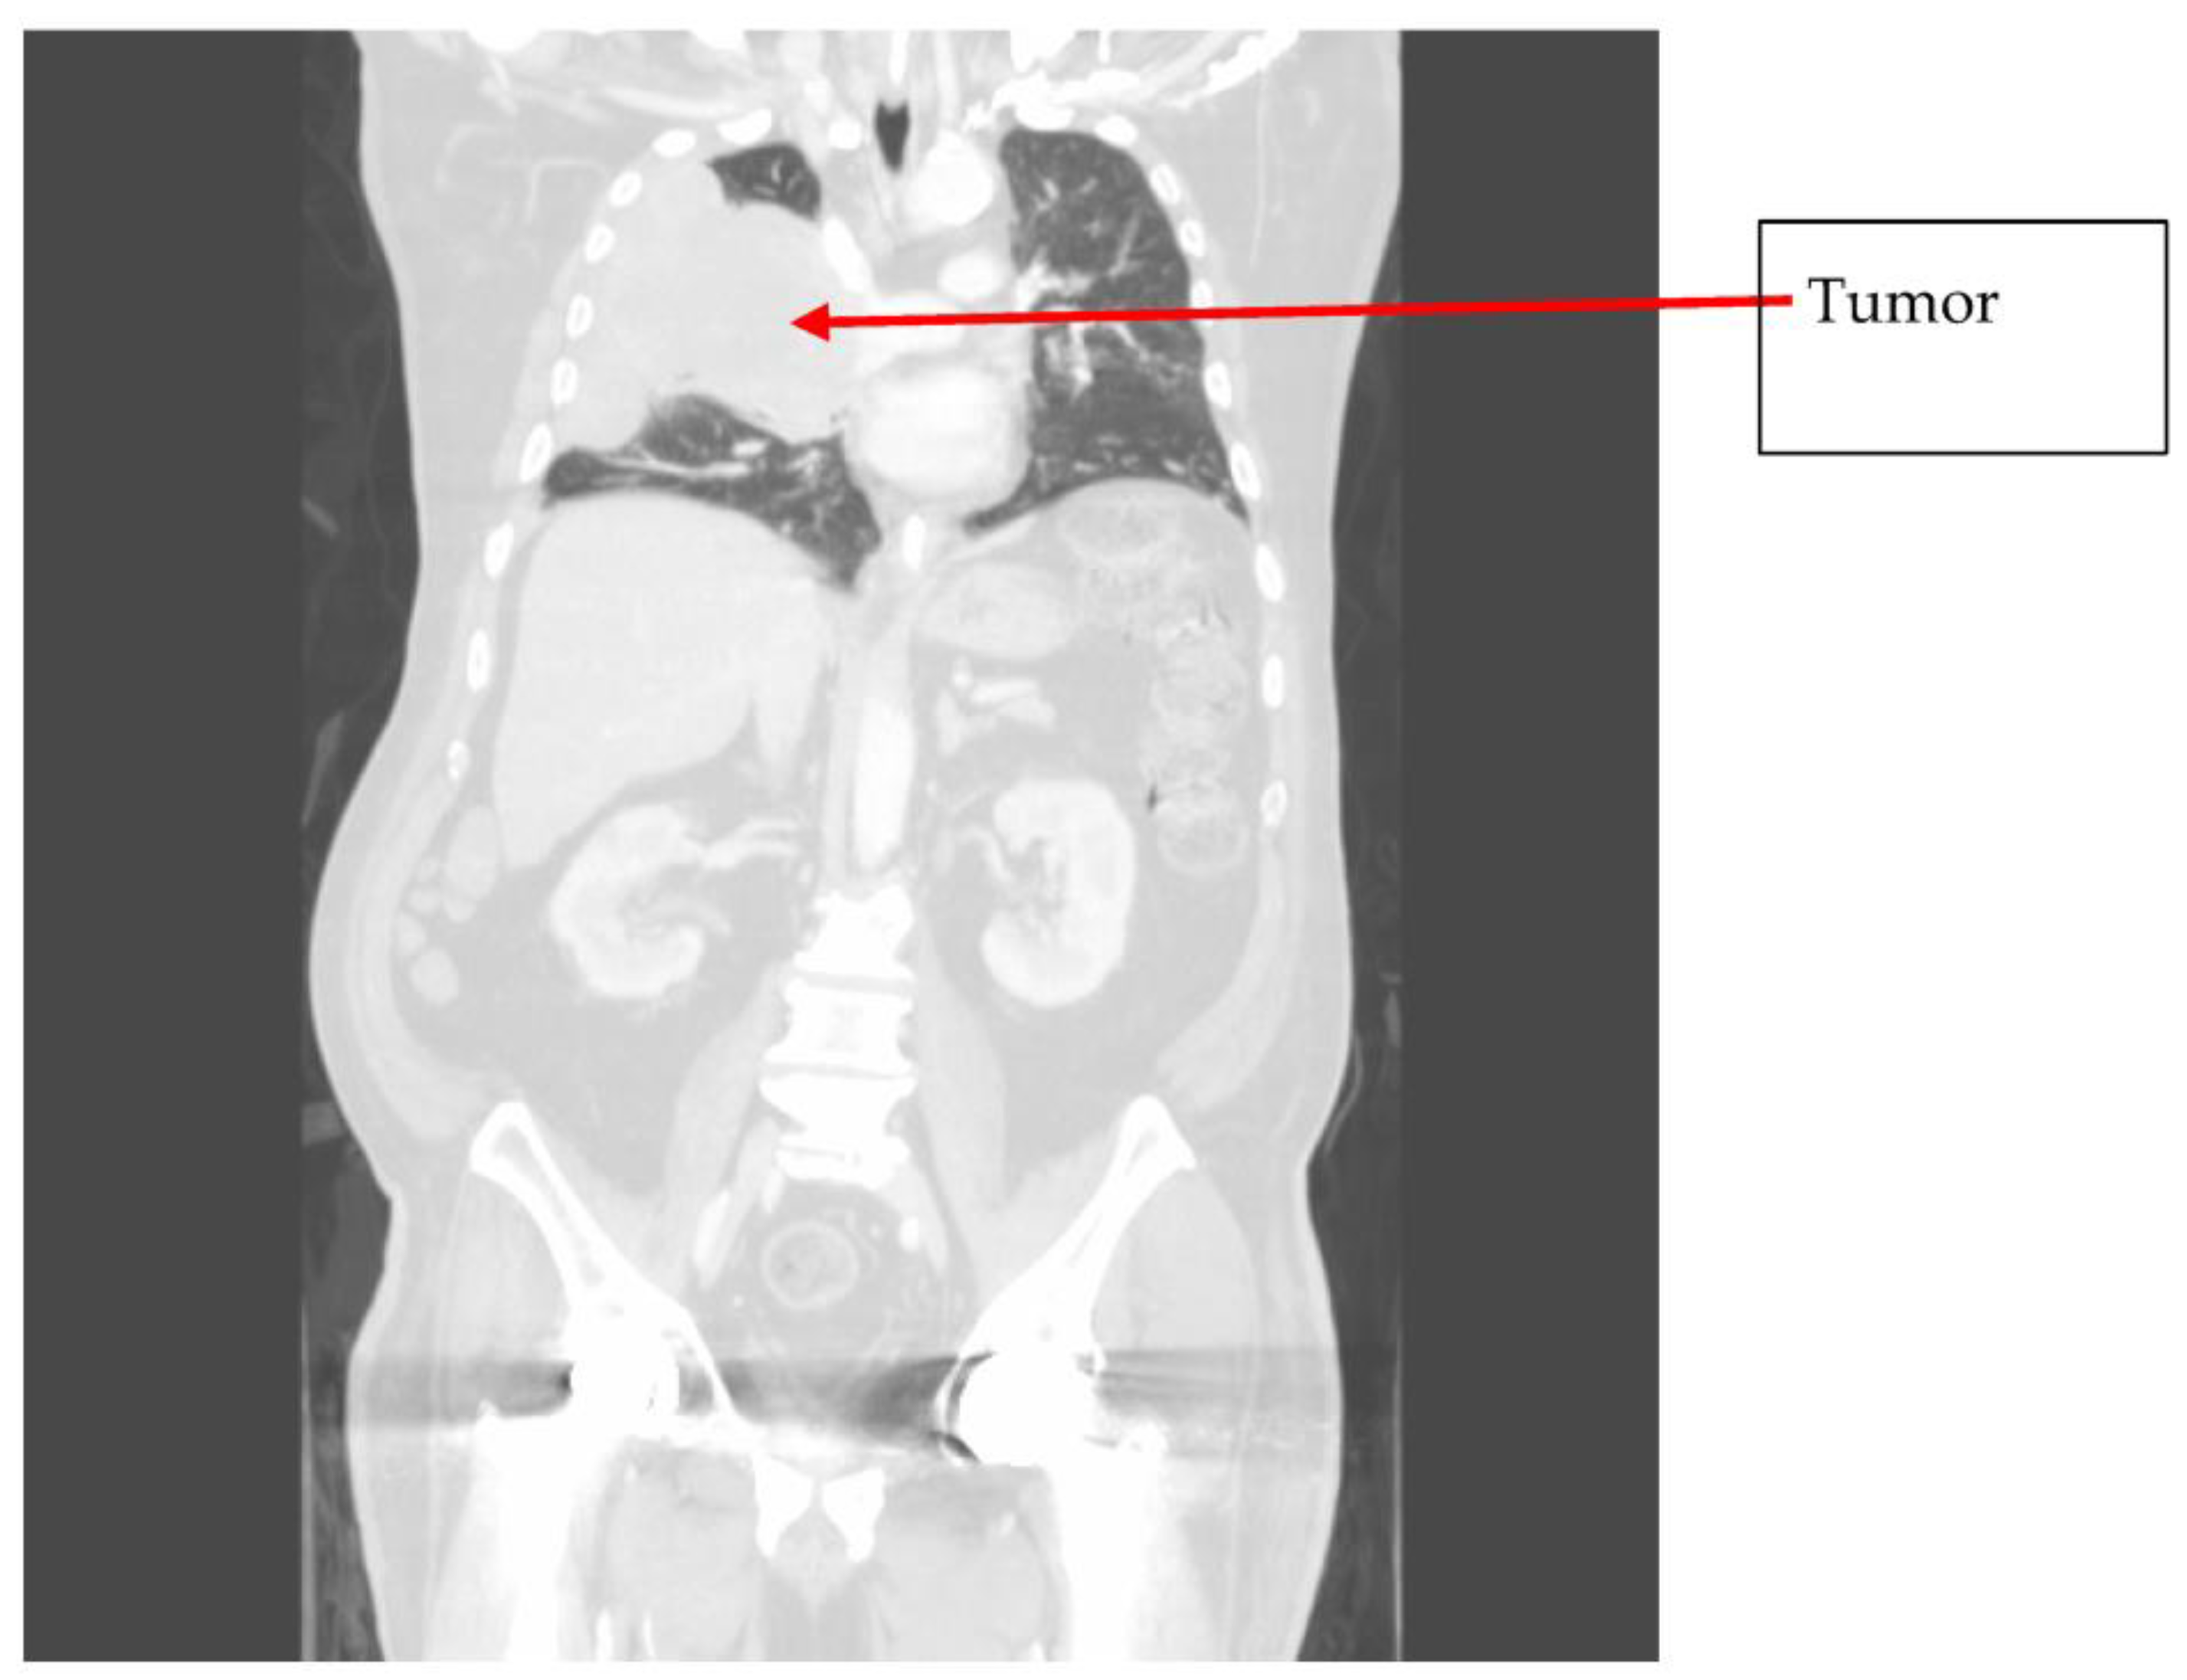

2. Case